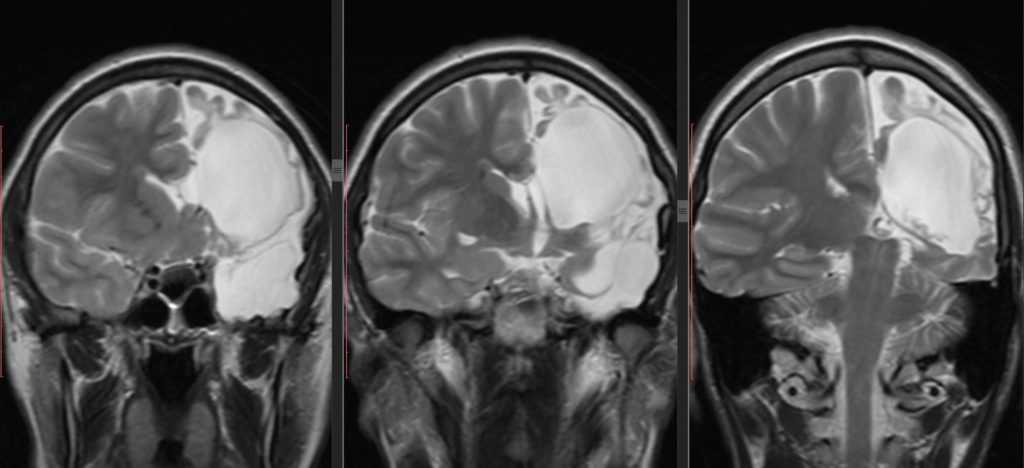

Клиника арахноидальной кисты не имеет специфичных проявлений и соответствует клинической картине, общей для большинства объемных образований головного мозга. К последним относятся внутримозговые и оболочечные гематомы, первичные и метастатические опухоли мозга, абсцесс головного мозга, внутримозговая киста. Осмотр невролога и первичное неврологическое обследование (электроэнцефалография, реоэнцефалография и эхо-энцефалография) позволяют установить наличие интракраниального образования с внутричерепной гипертензией и существующую судорожную активность головного мозга. Для уточнения характера объемного образования и его локализации необходимо проведение МРТ, СКТ головного мозга или КТ.

Оптимальным диагностическим методом для распознавания арахноидальных кист выступает МРТ головного мозга с контрастированием. Использование контрастных веществ позволяет отдифференцировать кисту от опухоли головного мозга. Основным критерием арахноидальной кисты, отличающим ее от опухоли, является отсутствие способности накапливать контраст. При помощи МРТ проводится дифференциальная диагностика с субдуральной гематомой, субарахноидальным кровоизлиянием, субдуральной гигромой, абсцессом, инсультом, энцефалитом и др. церебральными заболеваниями.